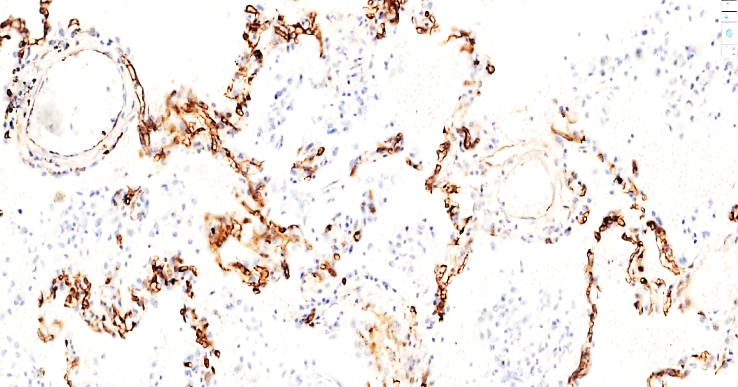

Paraffin-embedded biopsy materials were subjected to immunohistochemical examination using monoclonal antibodies using standard methods. The CD31 PECAM marker is a marker indicating the level of platelet-1, which adheres to the endothelium. The glycoprotein protein is mainly expressed on vascular endothelial cells, platelets, granulocytes, monocytes, and some T lymphocyte coreceptors, indicating the development of new vessels, and if it is present on the inner surface of the vessel, then thromboplastin is formed and the damage process on the inner surface of the vessel is acute.This glycoprotein is a transmembrane protein, and normally it does not react with the CD 31 PECAM marker and is not masked. Since the free location of these glycoproteins indicates the absence of intercellular contact, in our study, the complication of thromboembolism indicates the degree of vascular damage.This also means that this glycoprotein in the perivascular areas accelerates the process of angiogenesis by connecting other types of mesenchymal cells, and if the yellow-golden expression is detected on the inner surface of the vessels, it proves that the process of injury and thrombogenesis is taking place in these vessels.If, upon examination, it is detected in a scattered and irregular appearance in the stroma of the prevascular and intramural tissue, this means that the process of transformation of endothelial cells from mesenchymal cells and neoangiogenesis is taking place.In our study, there were 3 groups, and the lung tissue and small-caliber vessels of 18-44, 45-59, 60-74 years old were stained with the CD 31 PECAM marker. The following immunohistochemical analysis showed a high positive expression of the CD 31 PECAM marker in 6 out of 26 patients aged 18-44 years, which clinically and morphologically indicates a predominance of vascular damage at this age, and this indicates an acceleration of the process of thrombogenesis due to damage to the inner surface of small-caliber blood vessels of the lungs. The systemic appearance of leukotrienes and cytokines released from damaged tissues in the period after any type of surgical intervention indicates a predominance of the ability of the body to cause a systemic vascular response, mainly in 18-44 years, which also indicates a predominance of the body's age-related hyperergic response and the fact that in the period after thromboembolic complications, small-caliber vessels of the lungs are damaged mainly from small-caliber vessels. | Figure 1. A 41-year-old patient died of pulmonary embolism on the 4th day after surgery. Moderately positive expression of the CD 31 PECAM marker is detected in the intima of the alveolar walls and small-caliber vessels of the lung tissue. Staining is Dab chromogen. Size 20x10 |

| Figure 2. A 40-year-old patient died of pulmonary embolism on the 3rd day after surgery. Moderately positive expression of the CD 31 PECAM marker is detected in the intima of the alveolar walls and small vessels of the lung tissue. Staining is Dab chromogenic. Size 20x10 |